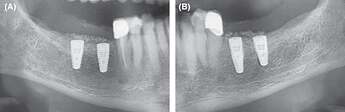

Figure 7.

Extracts from postoperative OPG after implantation and GBR in the third and fourth quadrant. A, fourth quadrant. B, third quadrant